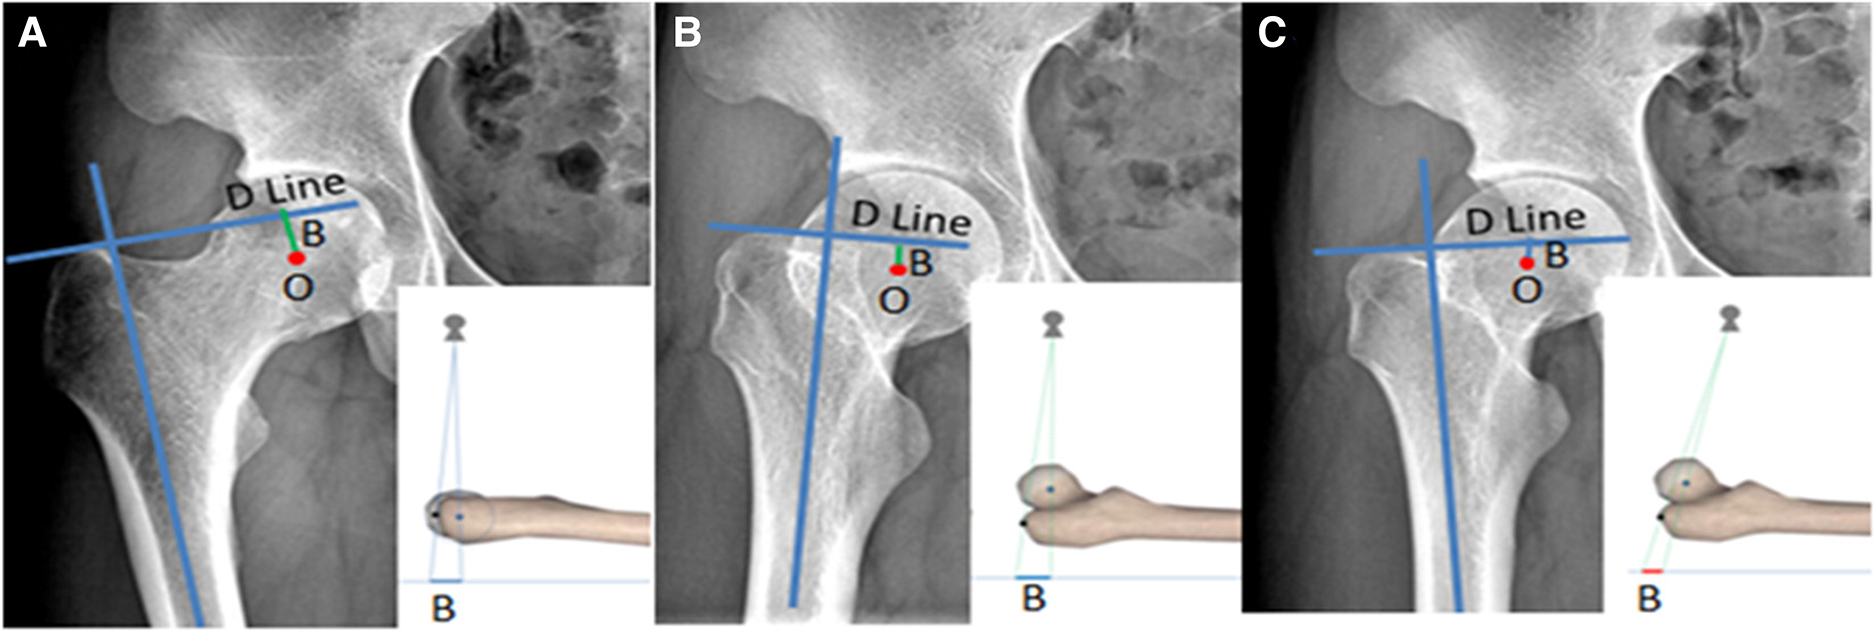

If the lower limbs are not sufficiently externally rotated, the center point of the femoral head and the apex of the greater trochanter will not be on the same plane due to the anteversion angle of the femoral neck. When this happens along with a very low projection point, the measured height of the femoral head will be significantly higher than the actual value, leading to postoperative extremity lengthening, as shown in Figure 7. The condition of five among eight patients with postoperative LLD > 10 mm in Group A was related to the substandard preoperative x-rays as described above.

Figure 7. Bilateral hip x-ray of the same volunteer: (A) is the standard photographic method as previously mentioned, (B) is the externally rotated hip and the projection point is standard, and (C) is the externally rotated hip and the projection point is 10 cm below the midpoint of the bilateral hips; the femoral head center is significantly higher than the actual value shown in (A).

It can be discerned from the above observation that hip external rotation and a low projection point will significantly influence the use of “Y” line technology (Figure 7). To avoid this influencing factor, when the lesser trochanter is found to be too large and the femoral calcar is not displayed clearly, or Shenton’s line is discontinuous on the preoperative x-ray, it is necessary to take an x-ray again under standard conditions, because these phenomena indicate that the internal rotation of the hip is insufficient and the projection point is dislocated.